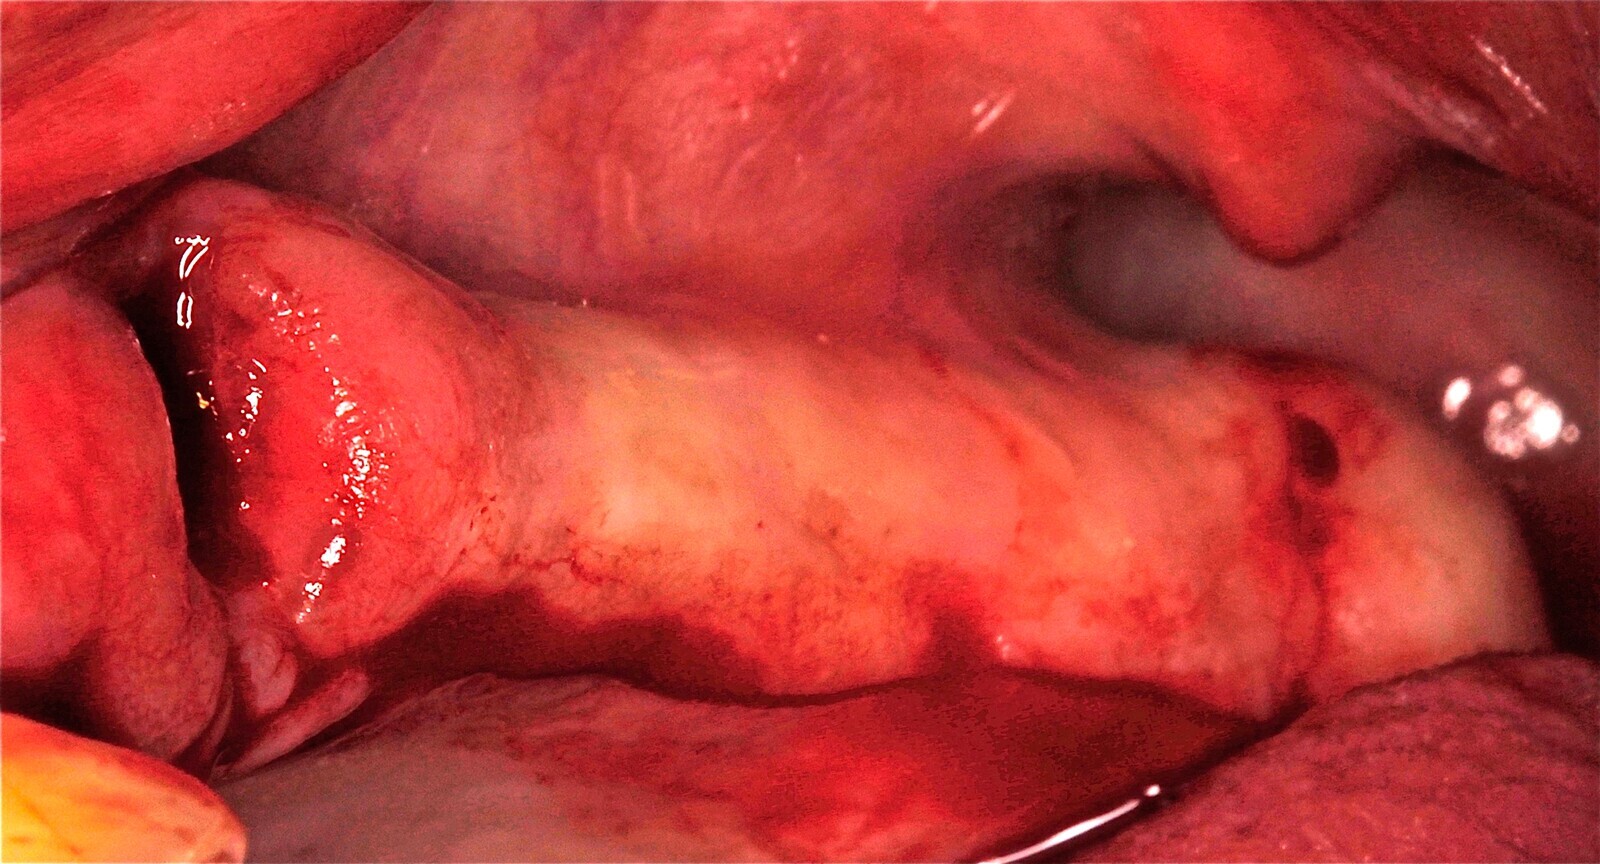

Fig. 15 Figura 15

5. Fijación del injerto previamente modelado al lecho con microtornillo de 1.5 a 2 mm de diámetro.

Fig. 16 Figura 16

6. Relleno de hueso particulado en la intersección entre el injerto óseo y el lecho receptor.

Fig. 17 Figura 17

7. Recubrimiento con una membrana reabsorbible o no reabsorbible para evitar la infiltración de tejido blando y garantizar la regeneración del defecto.

8. Fijación de la membrana con chinchetas para evitar su desplazamiento durante la reposición del colgajo.